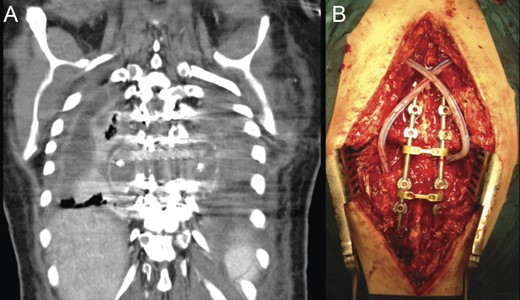

Due to the ongoing postoperative infection, a new operation was undertaken with surgical debridement of the infected tissues, allograft and titanium mesh extraction, which were replaced by iliac crest tricortical autograft for anterior support (Fig. 6). The posterior pedicle instrumentation was kept, after copious irrigation of the surgical wound. Drains were placed in the thoracic cavity and paravertebral spaces.

Revision procedure; a thoracotomy was performed for pus drainage and debridement, as well as removal of the anterior cage and allograft (A). A tricortical iliac bone autograft was used to maintain anterior-column stability (B). Postoperative radiographic study (C and D).

Concurrently, a newly resurged septated empyema had developed in the paravertebral space, which demanded for a combined anterior and posterior approach, for complete drainage (Fig. 7). Twelve days later, an additional posterior open drainage was necessary to address a subcutaneous abscess. Samples collected intraoperatively from this last operation isolated methicillin-resistant Staphylococcus aureus and Pseudomonas aeruginosa as pathogens.

(A) CT scan coronal reconstruction showing recurrence of paravertebral empyema. (B) Intraoperative image following posterior debridement.